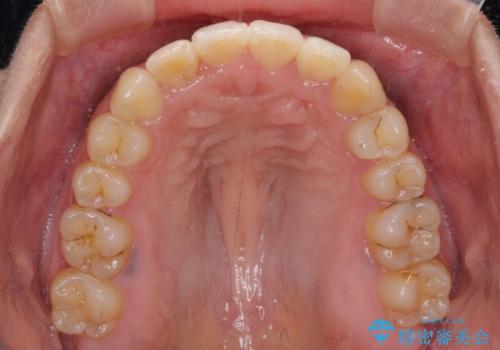

- 上下のデコボコを改善したいとのことで来院された患者様です。

近々妊娠する予定であり、極力短期間で治療したいとのことで、ワイヤー装置による非抜歯矯正治療を行うこととしました。